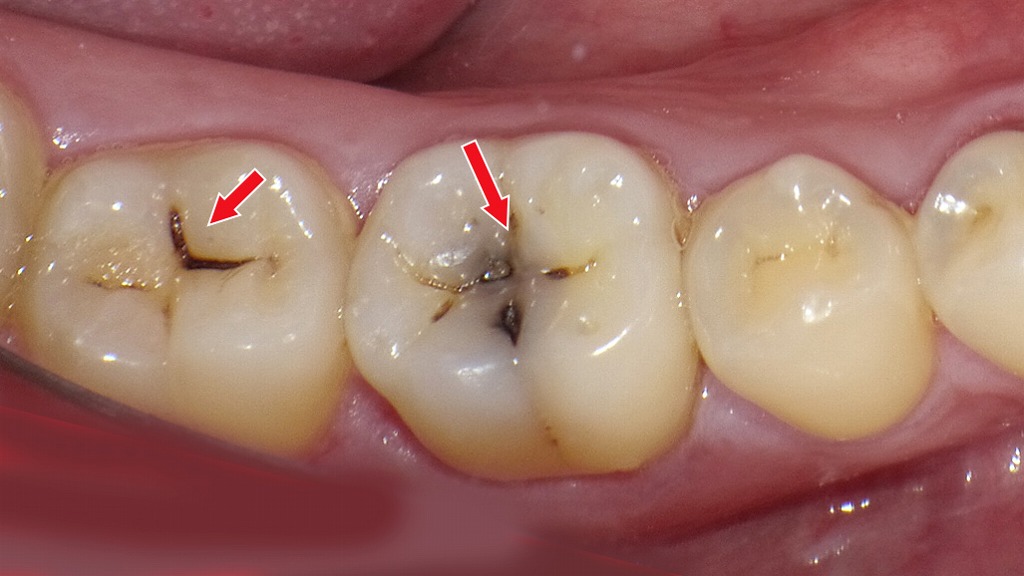

初期虫歯(C1)

初期虫歯(C1)は、虫歯がエナメル質の内部まで進行し始めた段階を指します。まだ穴は大きく開いておらず、痛みやしみる症状が出ないため、自覚しにくいのが特徴です。見た目としては、黒い点や小さな溝の変色として確認されることが多く、歯科医師による診断が重要になります。

C1でも削らずに治せるケースがある

C1は「削る虫歯」と認識されることが一般的ですが、予防処置が十分にできている場合は、削らず再石灰化で改善できるケースもあります。